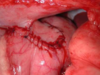

What type of gastropexy is this?

Belt loop gastropexy make a loop of stomach tunnel through transversus muscle